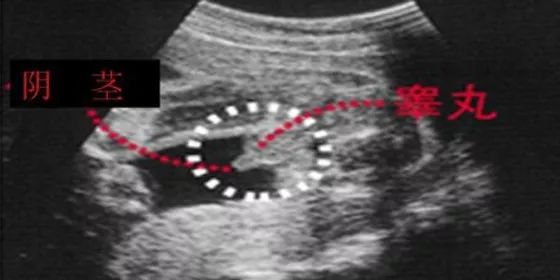

第三种:通过四维彩超图看清胎儿性别

男宝宝四维彩超图

“凸出的东西” 是他的标记: 你们看到圆圆的是蛋蛋,如果看到圆圆的加小肠的就是全部JJ